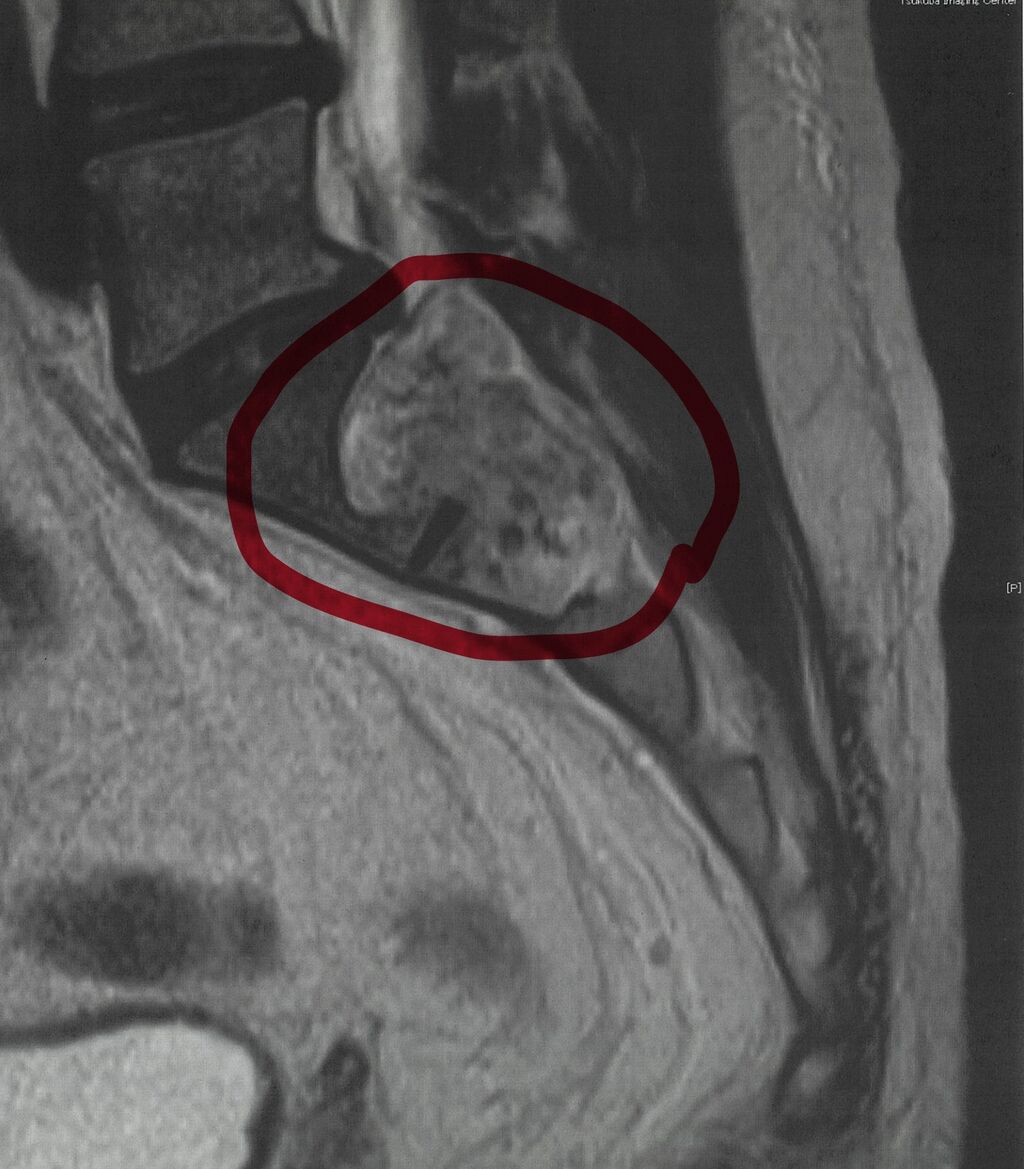

MRIを見せてもらうと腰の辺り、脊椎が見えるはずのところにしっかりと腫瘍がいた。記念に印刷してもらい持ち帰った。その写真がこれである。

医師の言うことには、おそらく良性の腫瘍、神経鞘腫だろうとのこと。脊椎のかなり下部であり、排尿障害や足のしびれがないのであれば放置していいらしい。一応気になるなら一年後に又診察とのこと。障害が出ていないのに下手に手術して神経が傷つくリスクは避けた方が良いらしい。